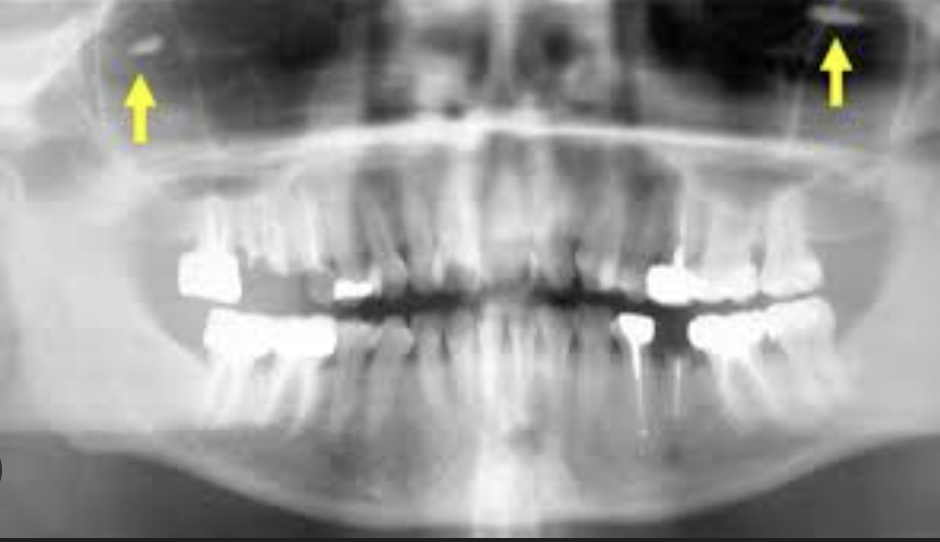

What is a ghost image?

This is when a real object on one side of the body is projected on the opposite side as more magnified, blurry, and higher up. It will have the same general shape as the object and will not be a mirror image.